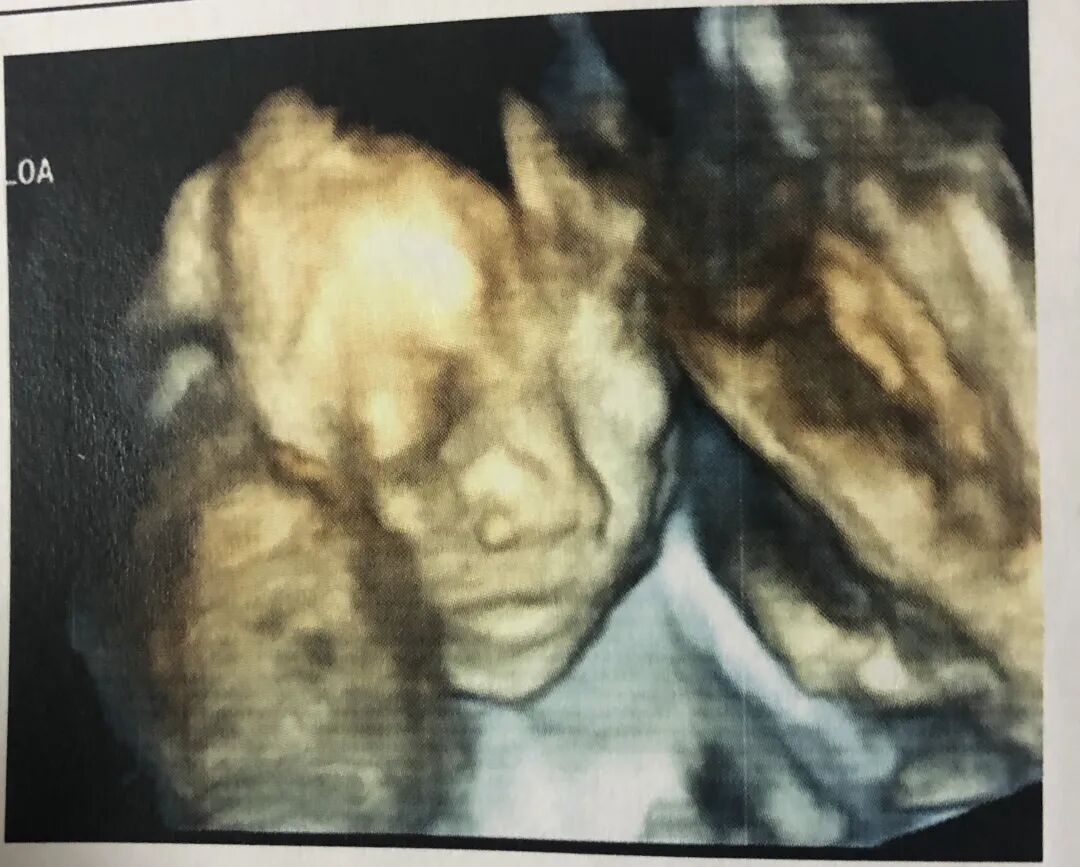

曦瑶的四维彩超照片

图源:作者供图